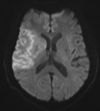

What is diffusion-weighted imaging, and why is it used in stroke?

DWI: Type of MRI sequence that measures diffusion of water molecules within tissues Highly sensitive to ischaemic changes

34

What does an ischaemic stroke look like on DWI brain?

Hyperdense lesion

Which 2 MRI sequences are used to identify ischaemic strokes, and what are the findings?

DWI T2-weighted & ADC: These sequences detect ischaemic changes within minutes to hours of onset, and DWI shows area of penumbra which guides treatment Ischaemic stroke findings: Hyperintensity on DWI and T2, hypointensity on ADC